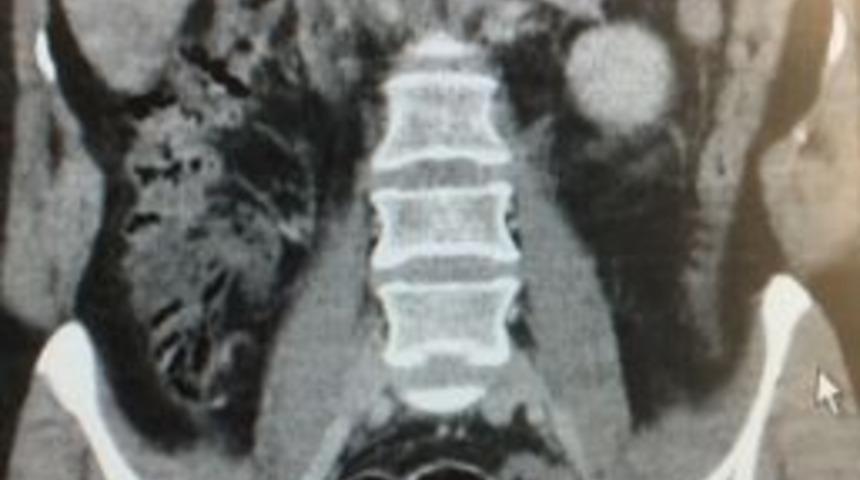

Muş’ta polisin istihabari bilgiler üzerine takibe aldığı Rus uyruklu kadın N.O.’nun midesinden 7 paket eroin ve metamfetamin maddesi çıktı.Edinilen bilgilere göre, Rus uyruklu kadın N.O. ve M.S.B. isimli şahıs hakkında Van’dan Muş’a uyuşturucu taşıdığı istihbaratı alan Muş Emniyet Müdürlüğü Narkotik Suçlarla Mücadele Şube Müdürlüğü ekipleri, şahısları takibe aldı.Şahısların hal ve hareketlerinden şüphelenen ekipler, şüpheliler üzerinde arama yaptı. Aramada şahıslar üzerinde uyuşturucu maddeye rastlamayan polis, şahısları gözaltına aldı. Gözaltına alınan şahıslar kontrol için Muş Devlet Hastanesine sevk edildi. Hastanede Rus uyruklu kadın N.O.’un çekilen röntgeninde yuttuğu anlaşılan 7 paket kalıp halinde eroin ve metamfetamin maddesi tespit edildi.Öte yandan midede uyuşturucu taşımanın dünyada nadir görülen bir yöntem olduğu öğrenildi.Şahıslar hakkında adli işlemler devam ediyor.